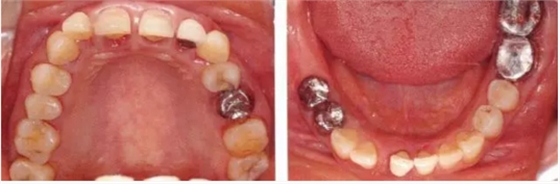

▲圖19-2,3

上下頜咬合面照。

▲圖19-4

X光片。牙槽骨明顯缺失。